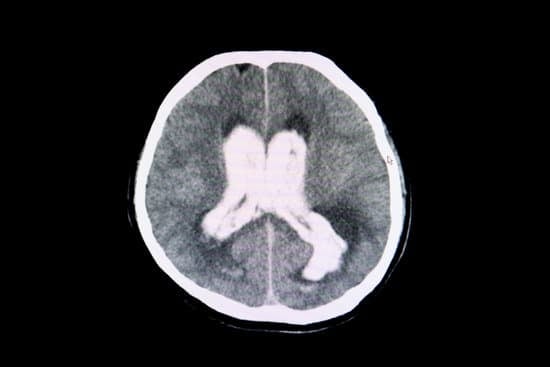

④ 뇌수종(수두증, Hydrocephalus)

✔ 뇌척수액이 과도하게 축적되어 뇌실이 확장됨

✔ 선천성 기형, 감염, 종양, 외상 등으로 발생

② 뇌 CT 또는 MRI 검사

✔ 뇌출혈, 뇌부종, 뇌종양, 수두증 확인

✔ 뇌실 확장 여부 & 구조적 이상 평가